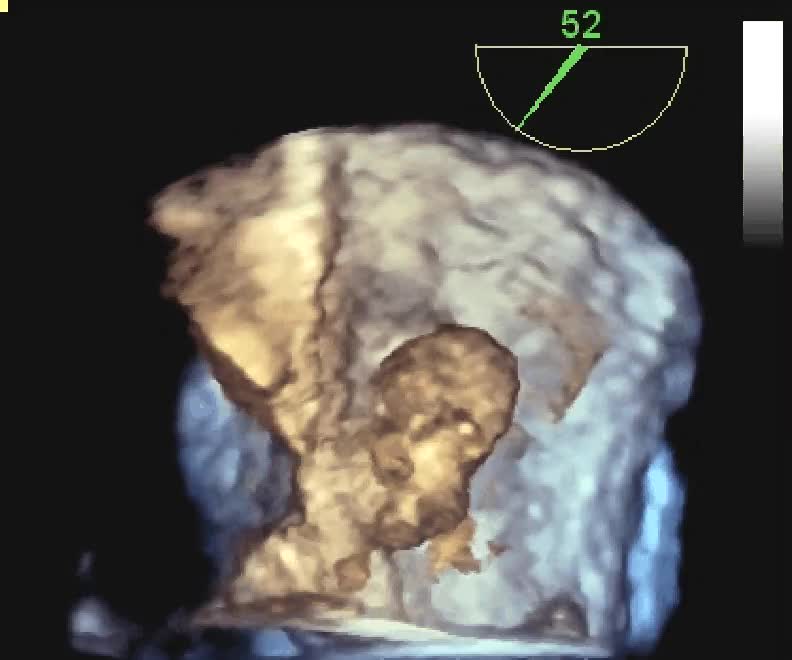

Vegetazioni su protesi mitralica biologica

Manuela Muratori